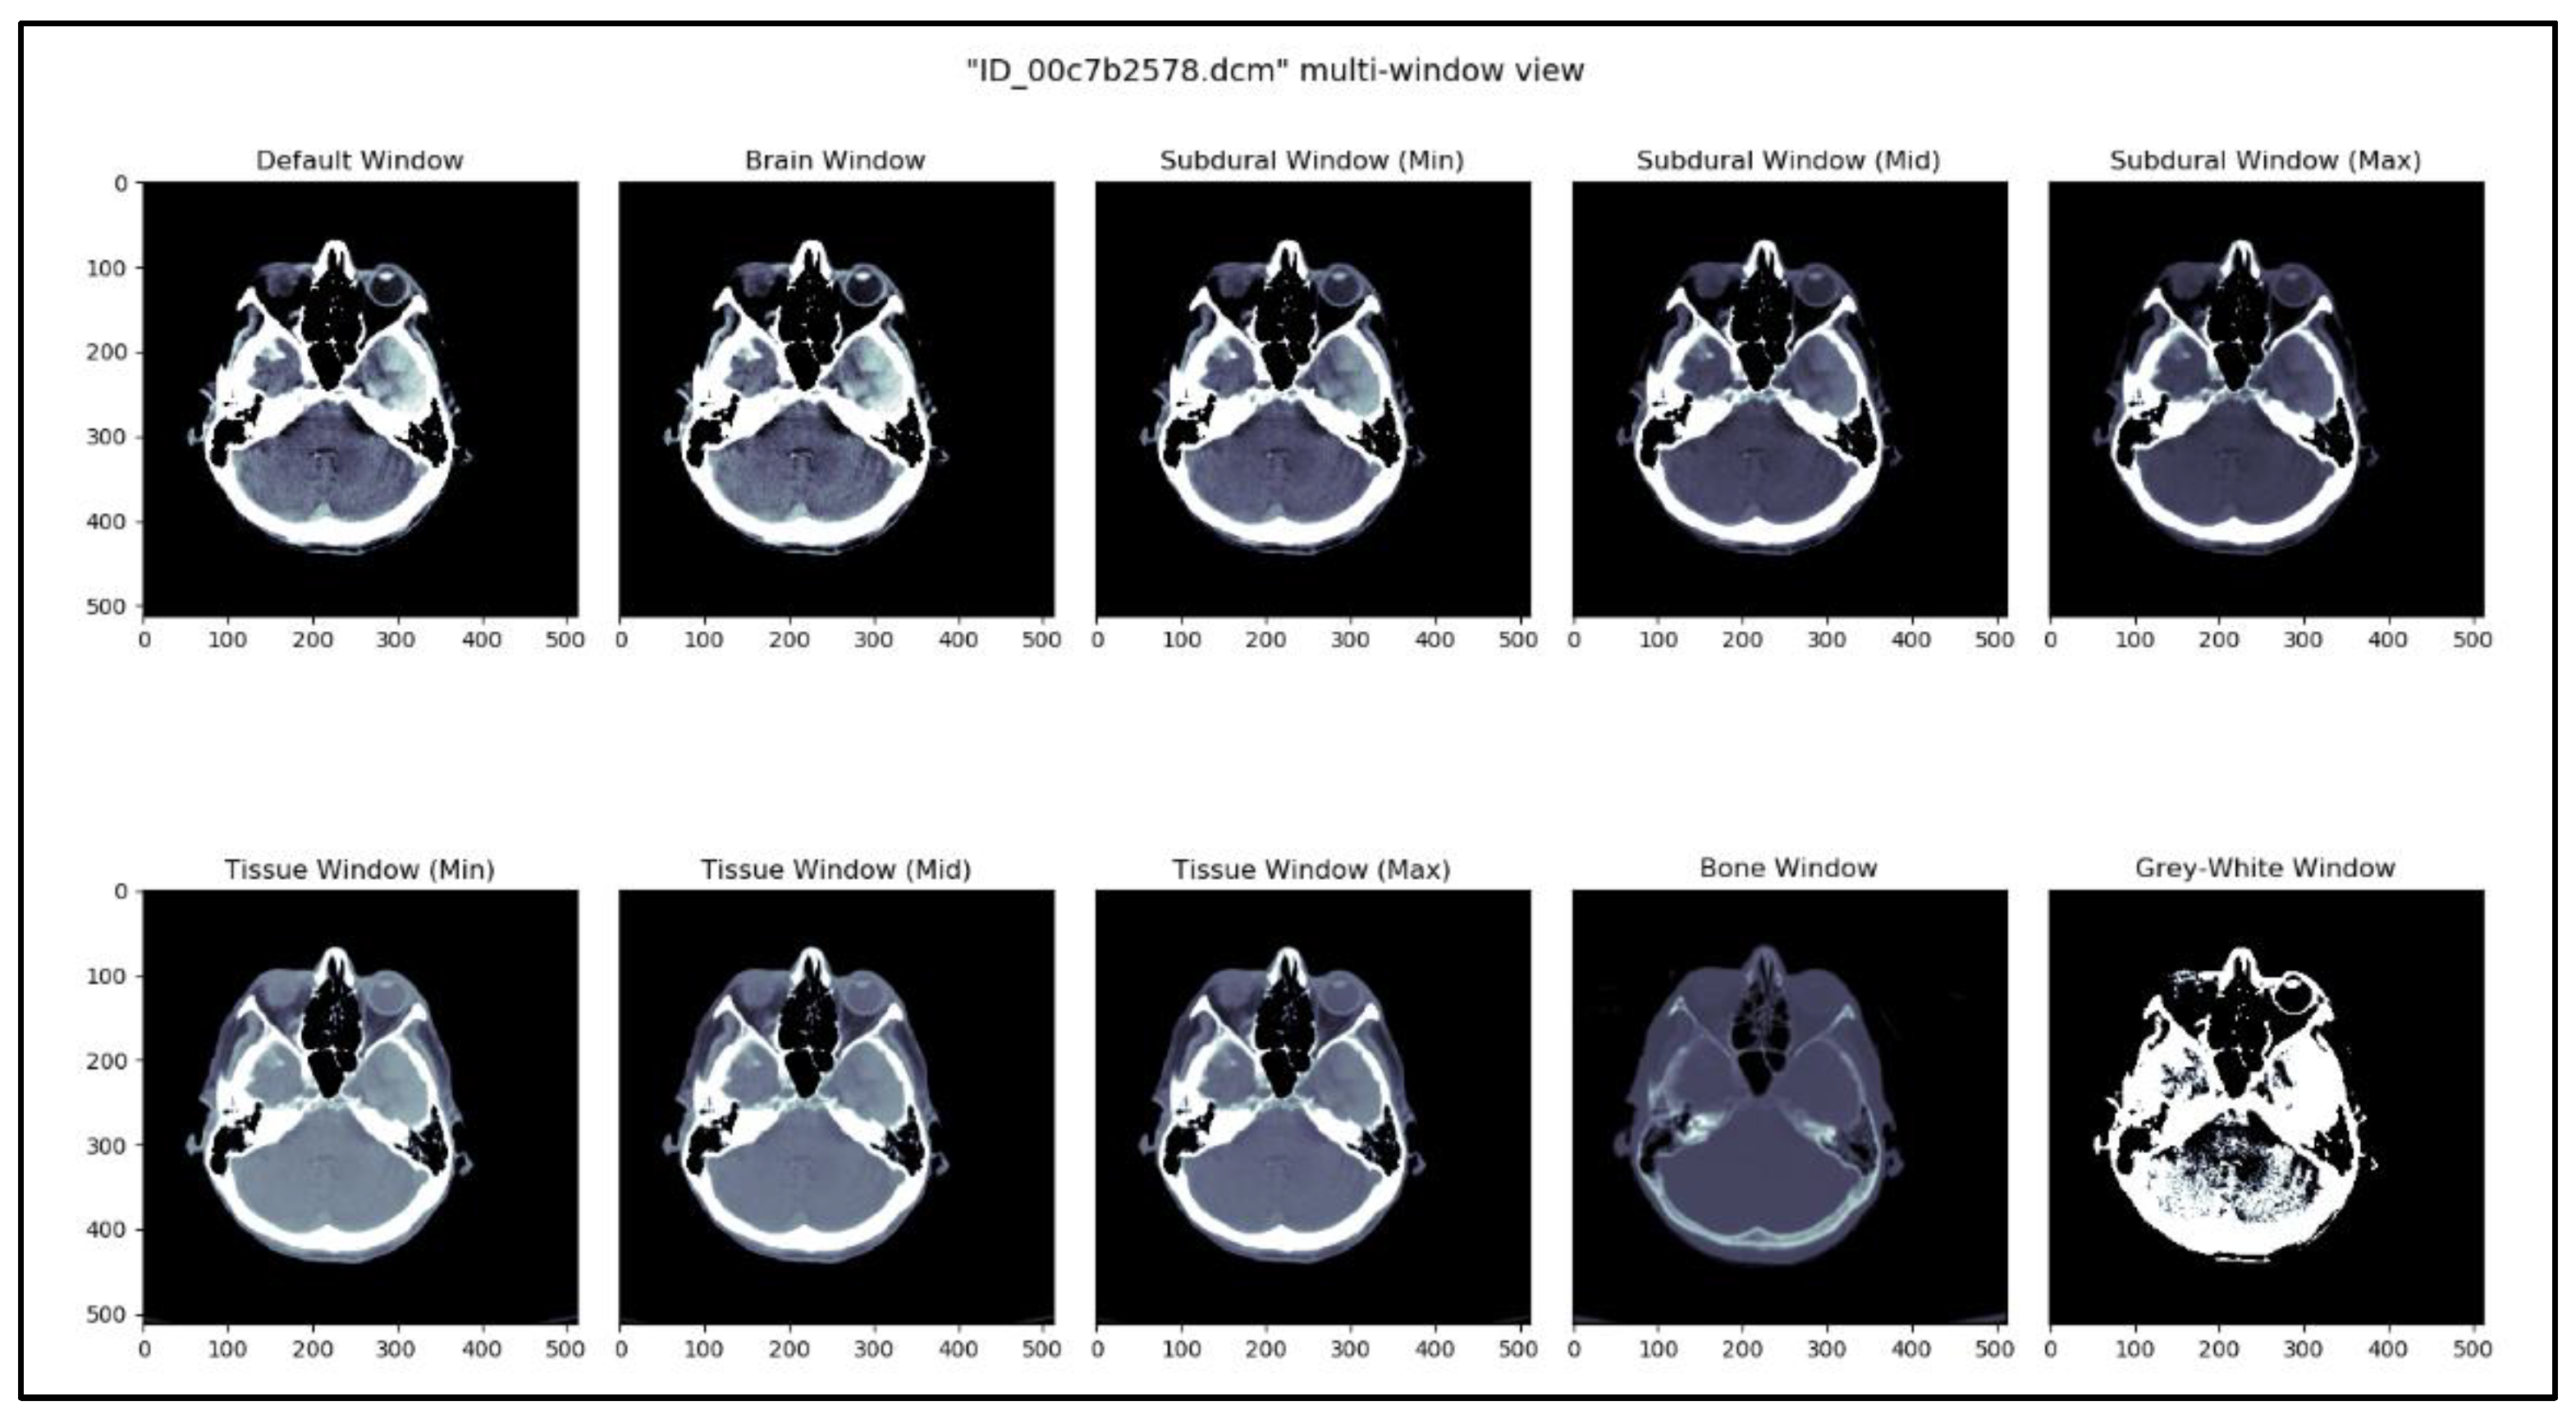

The kernel See like a Radiologist with Systematic Windowing [33] by David Tang discusses viewing DICOM files under various window settings before making a prognosis. This is the same strategy that radiologists utilize when reviewing CT scans in real-world scenarios. DICOM files vary depending on the window settings; certain hemorrhages are considerably simpler to identify under certain window settings. Windowing is used specifically for this purpose, reported in Table 4. Based on this kernel and our understanding of the process, ten window settings were chosen.

Table 4.

Different window settings.

This methodology creates a temporal sequence. All window settings mentioned in Table 2 are applied, and the result is stacked. Figure 3 shows 10 different views of the DICOM image using different window settings. Figure 4 shows the creation of a temporal series taken as input by CNN. CNN extracts the spatiotemporal data and identifies the significant features. Later, the LSTM model utilizes the CNN model’s output and performs the accurate prediction level in the CT scan.

Figure 3.

DICOM image viewed in 10 different window settings.